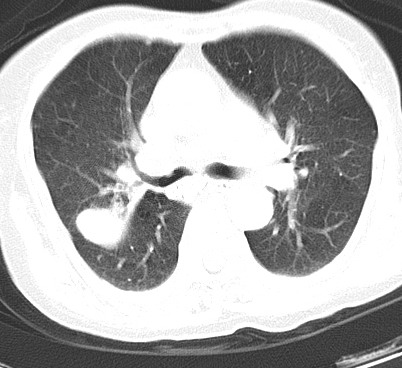

以下是引用hhcckk在2007-3-2 14:51:00的发言:[br]考虑结核球可能性大,依据[br]1病灶在下叶背段,结核的好发部位[br]2病灶内有大量的钙化,纵隔内有大量的淋巴结钙化[br]3重要的是半年前与现在相比无变化,假如是肿瘤的话不会这么‘善良’[br]4病灶周围卫星灶不明显,病灶有毛刺,胸膜凹陷,肿瘤不能完全排除,有条件的话最好做个活检

以下是引用liuyue在2007-3-2 17:15:00的发言:[br]1位置:右上叶后段[br]2性质:大分叶、粗长毛刺、条状斑片状钙化、纵隔多发淋巴结钙化,无强化,故考虑:肺结核灶(陈旧)